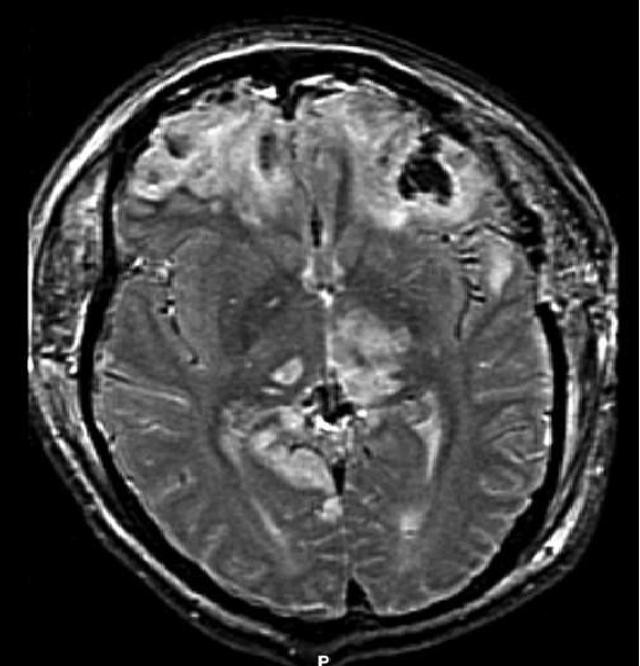

For instance, the development of Diffusion Tensor Imaging (DTI), an MRI-based technique, has been a game-changer. DTI allows for the visualization of white matter tracts in the brain. It often highlights subtle injuries associated with TBIs that traditional scans might miss.

Similarly, Functional Magnetic Resonance Imaging (fMRI) innovations provide deeper insights into real-time brain activity. They pinpoint trauma-affected areas and aid in more precise interventions.